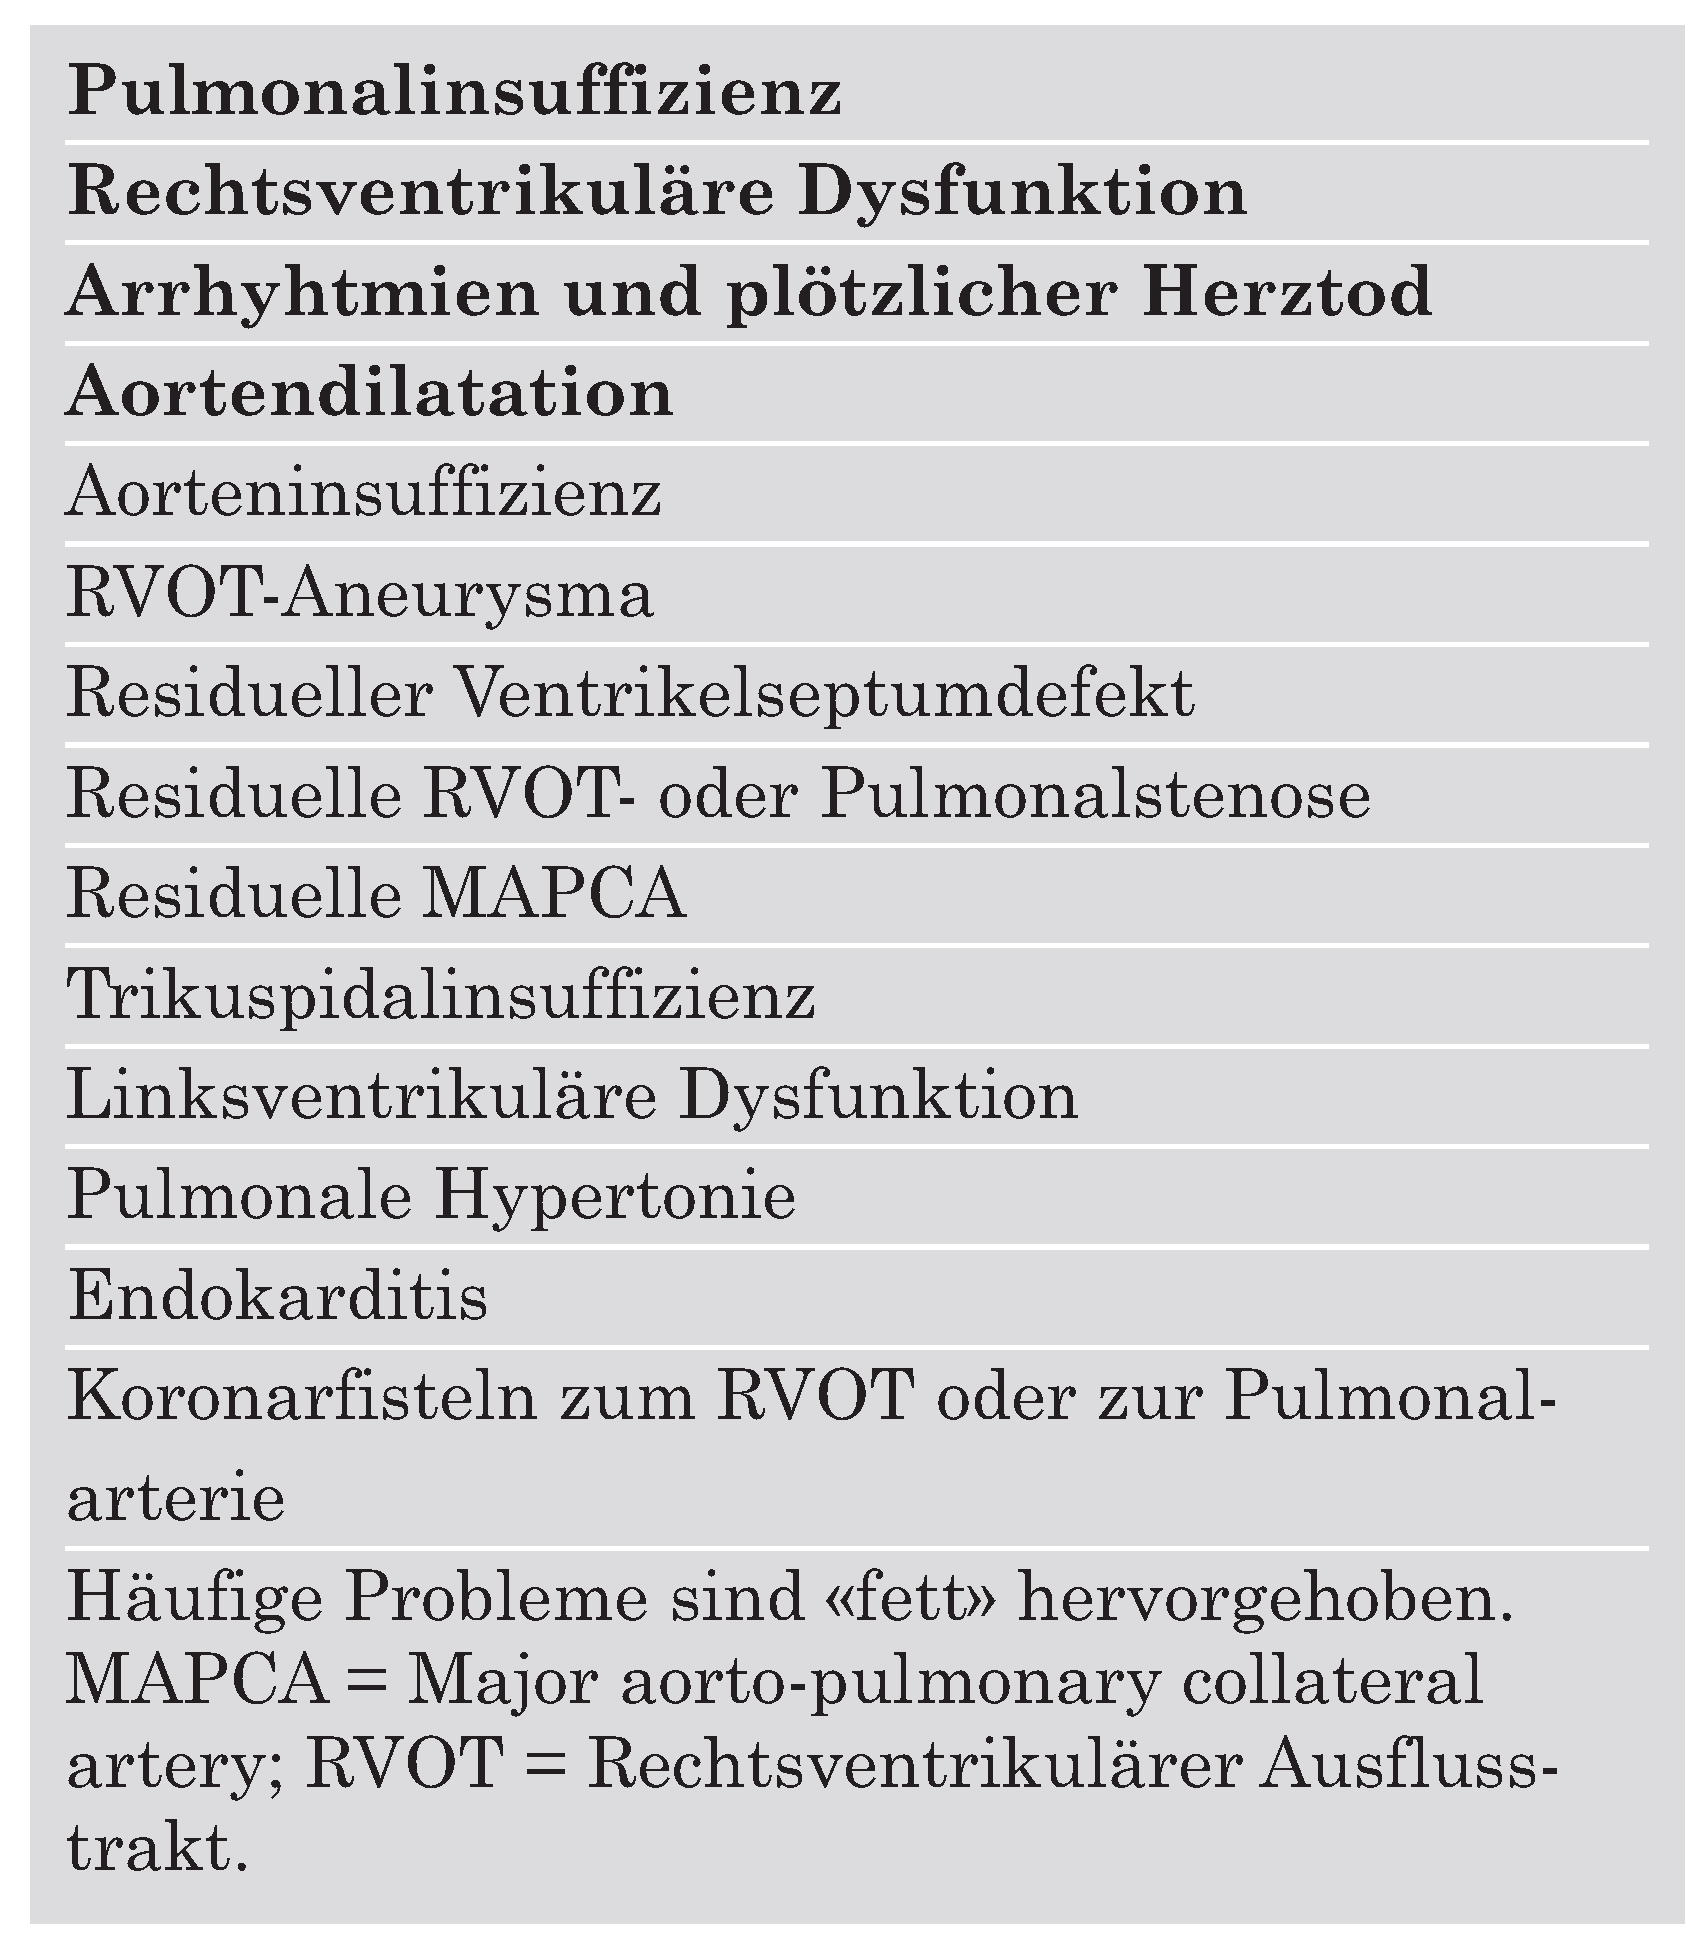

Tabelle 1 macht deutlich, inwieweit der Begriff «Fallot-Totalkorrektur» irreführend ist.

Die negativen Folgen der Pulmonalinsuffizienz sind wiederholt beschrieben worden: Eine progressive Abnahme der RV-Funktion und Zunahme der RV-Volumina, Häufung von atrialen und ventrikulären Arrhythmien und damit verbunden ein erhöhtes Risiko des plötzlichen Herztodes [

23]. Herzinsuffizienz und plötzlicher Herztod sind die häufigsten Todesursachen des adulten «korrigierten» Fallot-Patienten. In einer vielzitierten retrospektiven Studie wurde beobachtet, wie 25 Jahre nach Fallot-Korrektur die postoperative Mortalität von 0,24%/Jahr auf 0,94%/Jahr anstieg [

24]. Insbesondere die Häufigkeit des plötzlichen Herztodes, wahrscheinlich aufgrund von Arrhythmien, nimmt 20 Jahre nach der Korrektur-Operation deutlich zu und dürfte unter anderem auf die negativen Langzeitfolgen einer schweren Pulmonalinsuffizienz zurückzuführen sein. Ein transanulärer Patch mit der Prädisposition zur schweren Pulmonalinsuffizienz sowie eine progressive Verlängerung der QRS-Dauer sind mittlerweile etablierte Prädiktoren des plötzlichen Herztodes beim adulten «korrigierten» Fallot-Patienten [

25].